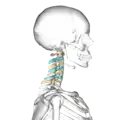

Shape of cervical vertebrae (shown in blue and yellow). Animation.

Cervical vertebrae, lateral view (shown in blue and yellow)